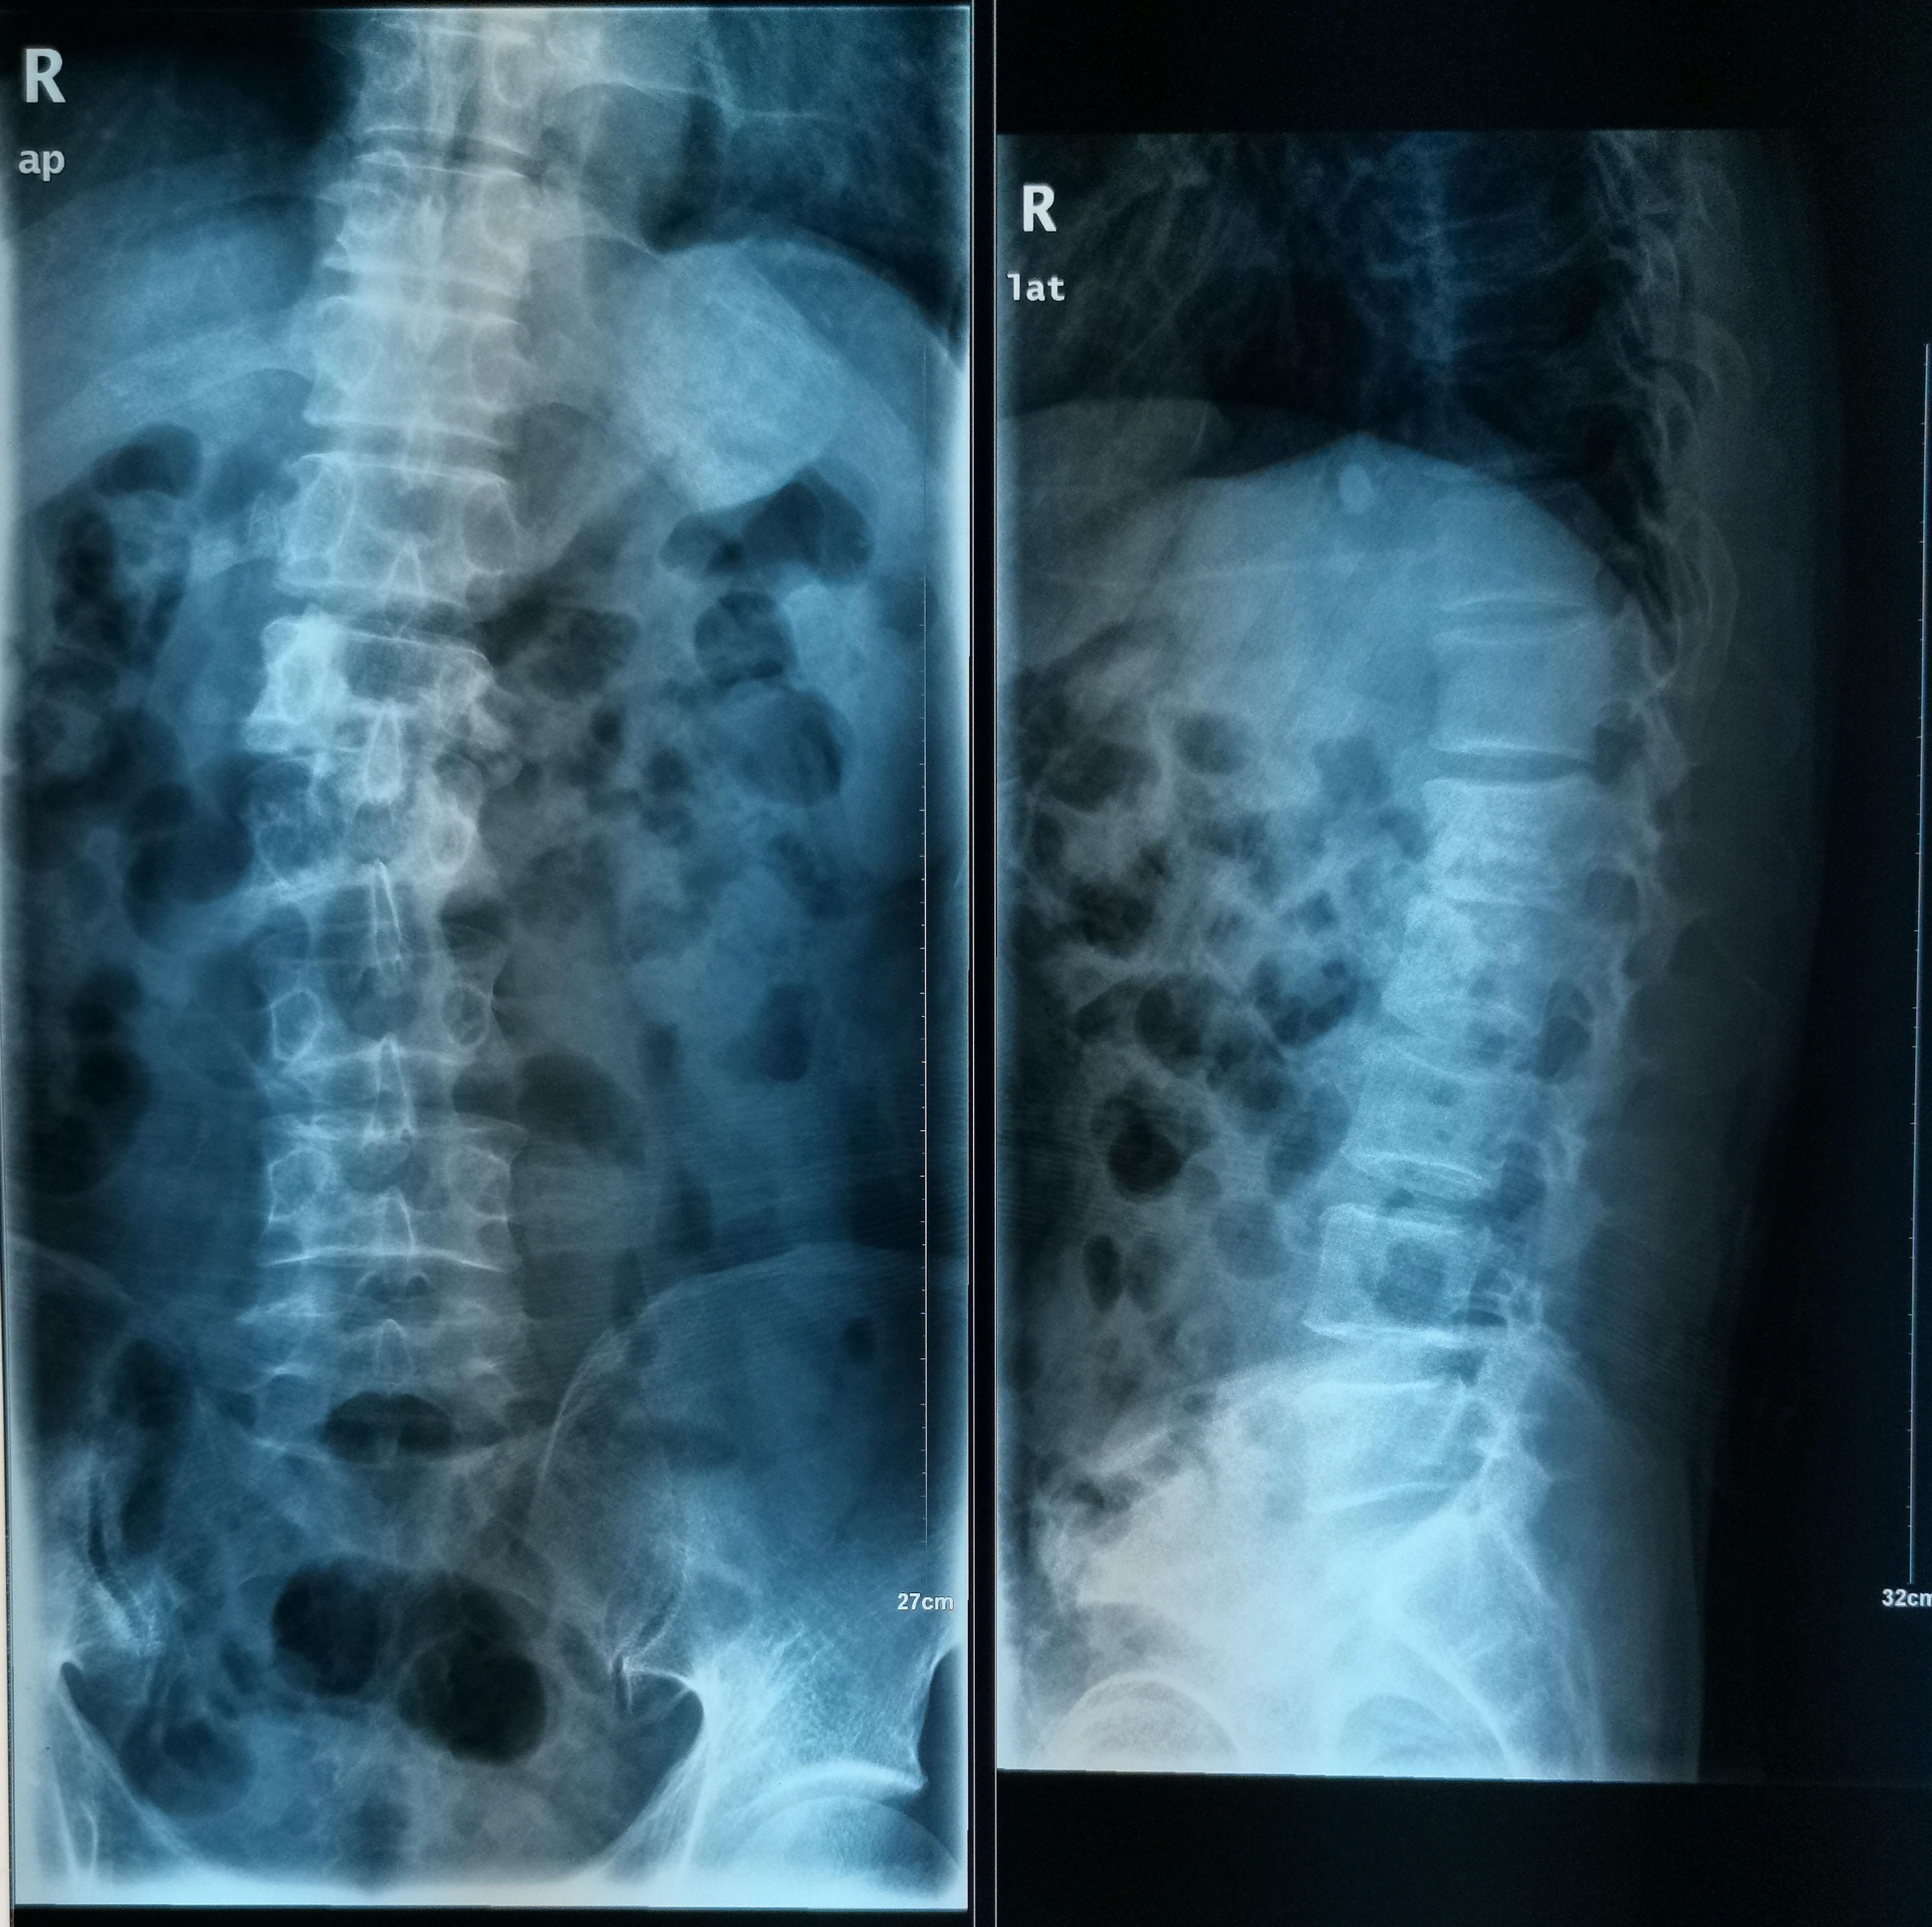

腰椎病变(比如图示腰椎脊柱结核)同样可引起脊柱侧弯

退行性脊柱侧弯 这种脊柱侧弯多见于老年人,随着年龄的增加侧凸程度会逐渐加重,是由于腰椎椎间盘、关节突的退变,长期脊柱失稳等原因导致脊柱排列改变,是脊柱退化的结果。

退行性脊柱侧弯多见于老年人,与脊柱退变有很大关系